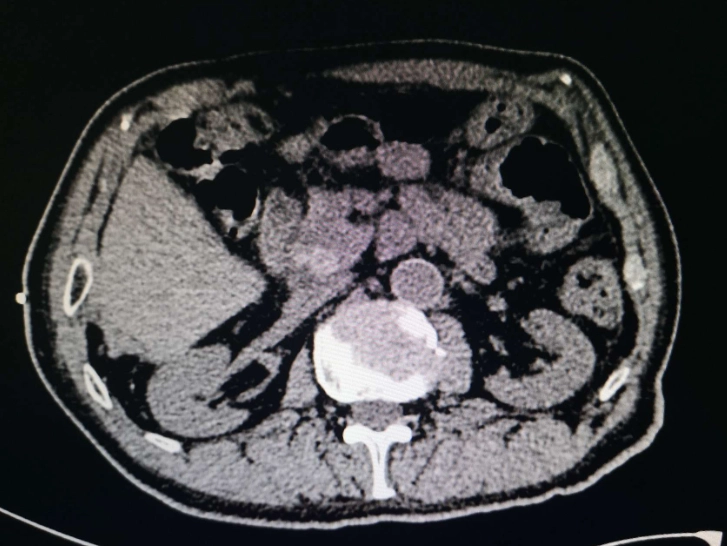

診斷胰線炎,主要靠血液檢查和影像學檢查。血液檢查會測澱粉酶和脂肪酶,這兩種酶在胰線炎時會升高。但注意,升高不一定就是胰線炎,其他疾病也可能,所以需要影像確認。

影像檢查包括超音波、電腦斷層(CT)或磁振造影(MRI)。超音波可以看膽結石,CT則能詳細顯示胰腺發炎程度。我有個朋友做CT後,醫生發現胰腺周圍有積液,確診為中度急性胰線炎。